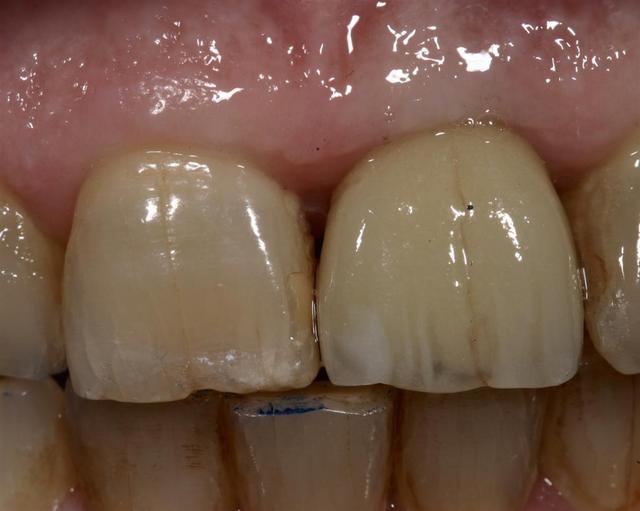

Allez, pour apporter mon caillou à la plage, un cas intéressant, d'implant en urgence.

consultation suite à une chute et fracture de 21 couronnée, un 29 Décembre, décision de poser l'implant le 31.12.

Extraction, mise en place d'un implant de 5*11.5 torque > 35N

Mise en place d'une dent provisoire transvisée.

Prothèse transvisée définitive à 3 mois.

Les 2 dernières photos à 1 an.

la photo ceram en place est à 6 mois. Noter l'amélioration des papilles entre 6 mois et 1 an...